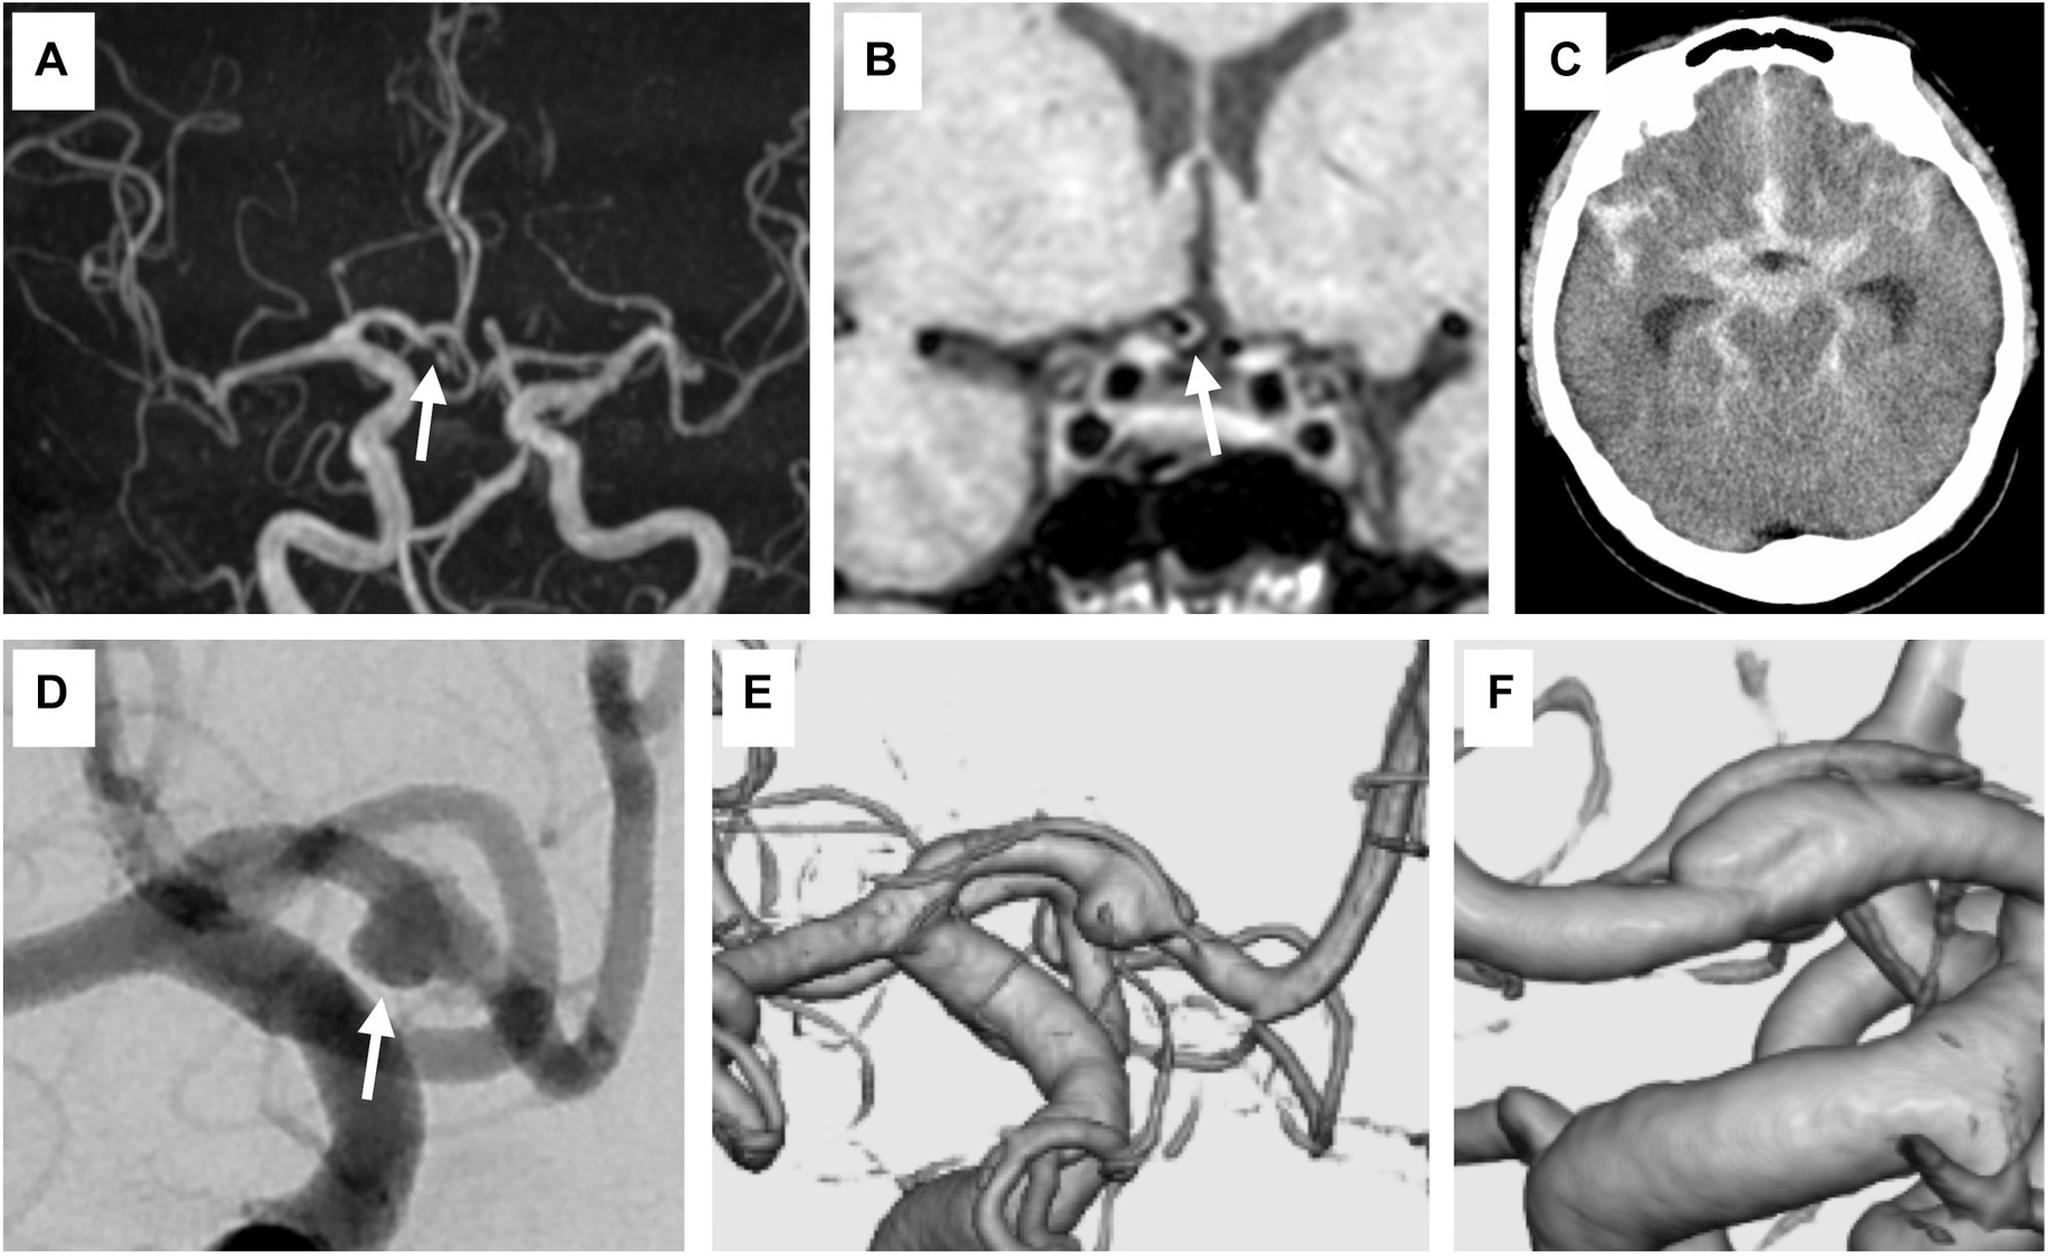

A 51-year-old woman developed subarachnoid hemorrhage the day after transient left hemiparesis. Angiography revealed a ruptured anterior cerebral artery dissecting aneurysm. We conducted stent-assisted coil embolization with the overlapping stent technique on the day after the hemorrhage. She recovered steadily without rebleeding. Six months after embolization, no recurrence was found on angiography.

一名51岁女性在短暂性左侧偏瘫后次日发生蛛网膜下腔出血。血管造影显示大脑前动脉夹层动脉瘤破裂。我们在出血后次日采用重叠支架技术进行了支架辅助弹簧圈栓塞。她恢复平稳,未再出血。栓塞6个月后,血管造影未发现复发。